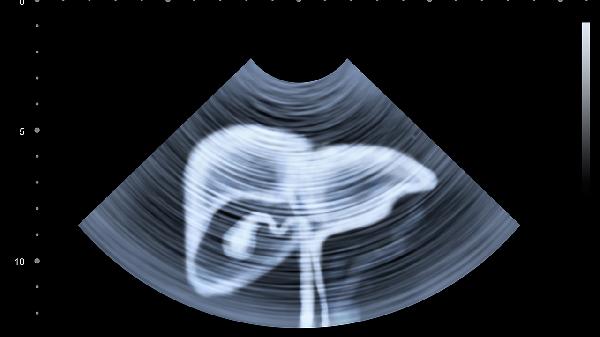

1、体检要查"肝功+超声+甲胎蛋白"